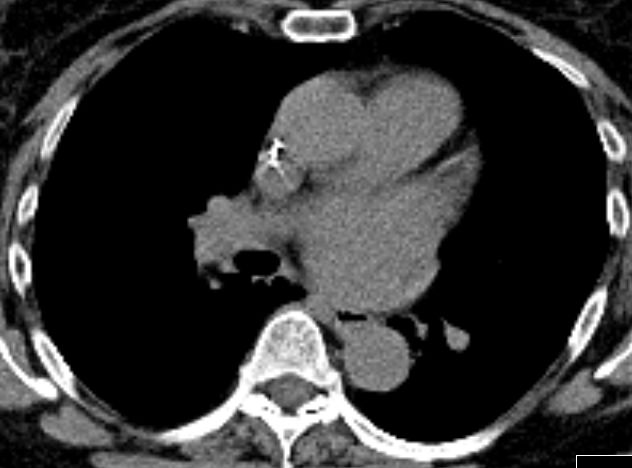

58-jährige Frau mit CUP. Beim Schlucken Beschwerden im mittleren Thoraxbereich. Oberhalb der Trachealbifurkation ist die Speiseröhre gering gefüllt.

Der linke Hauptbronchus komprimiert den Ösophagus.

Unterhalb des linken Hauptbronchus ist die Speiseröhre leer..